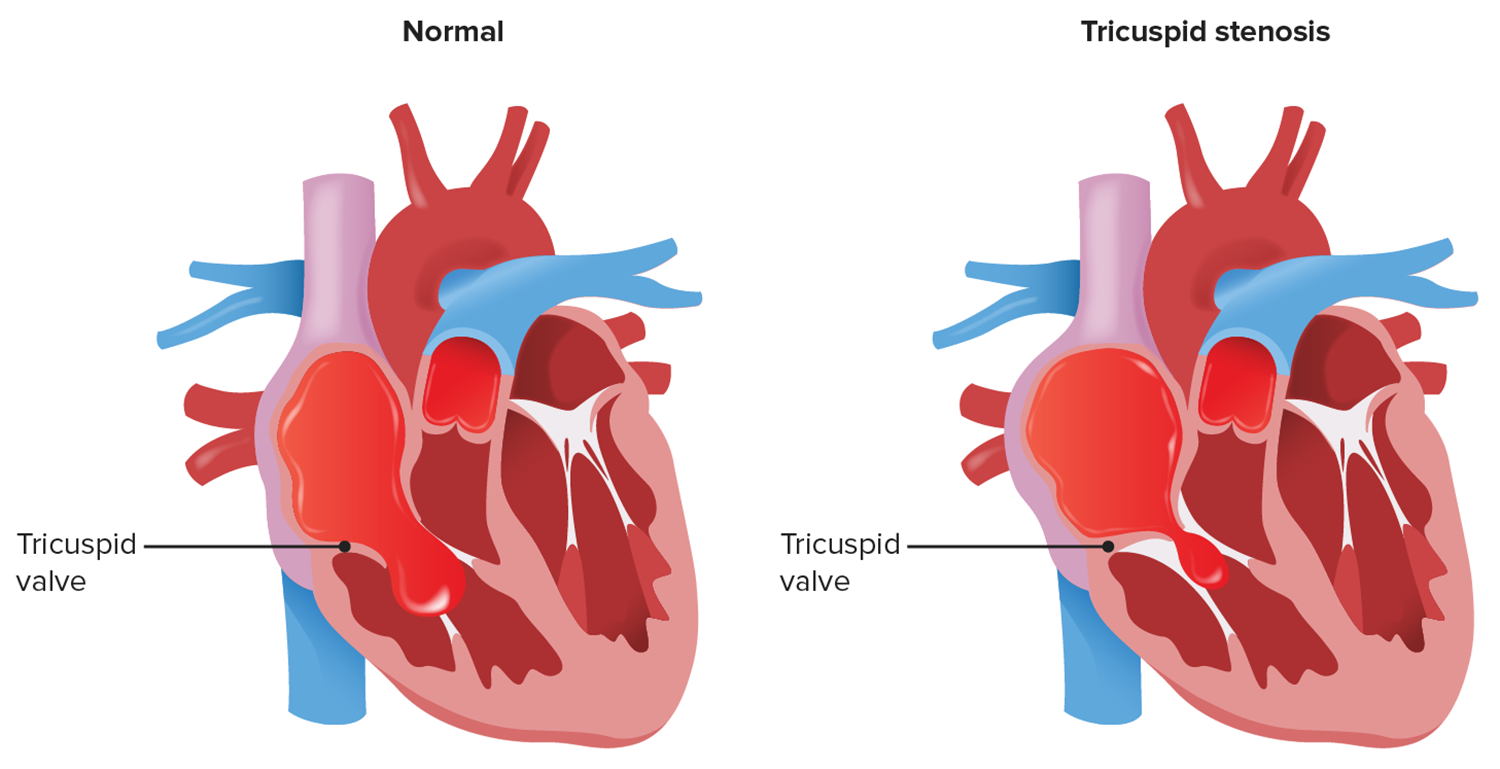

What is TV stenosis?

A condition in which the valve between RA and LA are not functioning properly. Tricuspid stenosis often occurs with other heart valve problems.

A narrowing of the tricuspid valve orrifice that impedes diastolic flow traveling from RA>TV>RV

Tricuspid Stenosis

Tricuspid stenosis causes a

reduction of blood from the RA into the RV

Tricuspid Valve Stenosis causes the______to become enlarged, decreasing the amount of blood entering the _____.

RA/RV